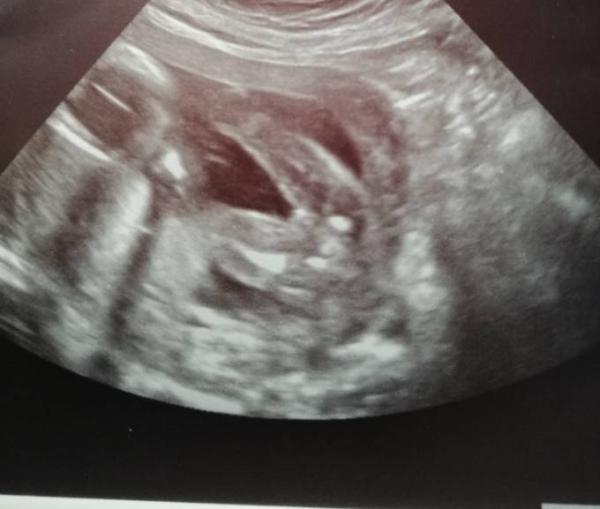

Huhu Ich habe heute laut Arzt ein 95% Outing bekommen Hat wer hier ein ul Bild und es ist wirklich auch sondases ein Mädel ist? (vielleicht vom Bluttest bestätigt)

Bild zu frage Mädchen - Forum für Juni - Mamis

Also ich gehöre ja ehr zu denen die Stundenlang aufs Bild schielen und nichts erkennen. Aber das sieht sehr deutlich nach Mädchen aus!

Hallo, ich habe nur ein US Bild vom Jungsouting, dass sieht ganz anders aus als deines. Bei meinem Mädchen sah es so aus wie bei dir. Ich finde es sehr eindeutig. LG

Huhu, ich erwarte einen Jungen und das sieht auf jeden Fall ganz anders aus. Bei dir ist das eindeutig ein Mädchen.

Das sieht man zu 100% dass es ein Mädchen ist. Ich habe 3 Mädels (2010, 2012, 2018) und kenne mich da aus. Diesmal wird es bei mir ein Junge und es sieht ganz anders aus.

Hallo Ich bekomme auch ein Mädchen Habe es zweimal vom Arzt bestätigt bekommen .Da ich schon zwei Jungs habe kann ich dir auch sicher bestätigen das du ein Mädchen bekommst .Sieht bei mir ähnlich auf dem Ultraschall aus